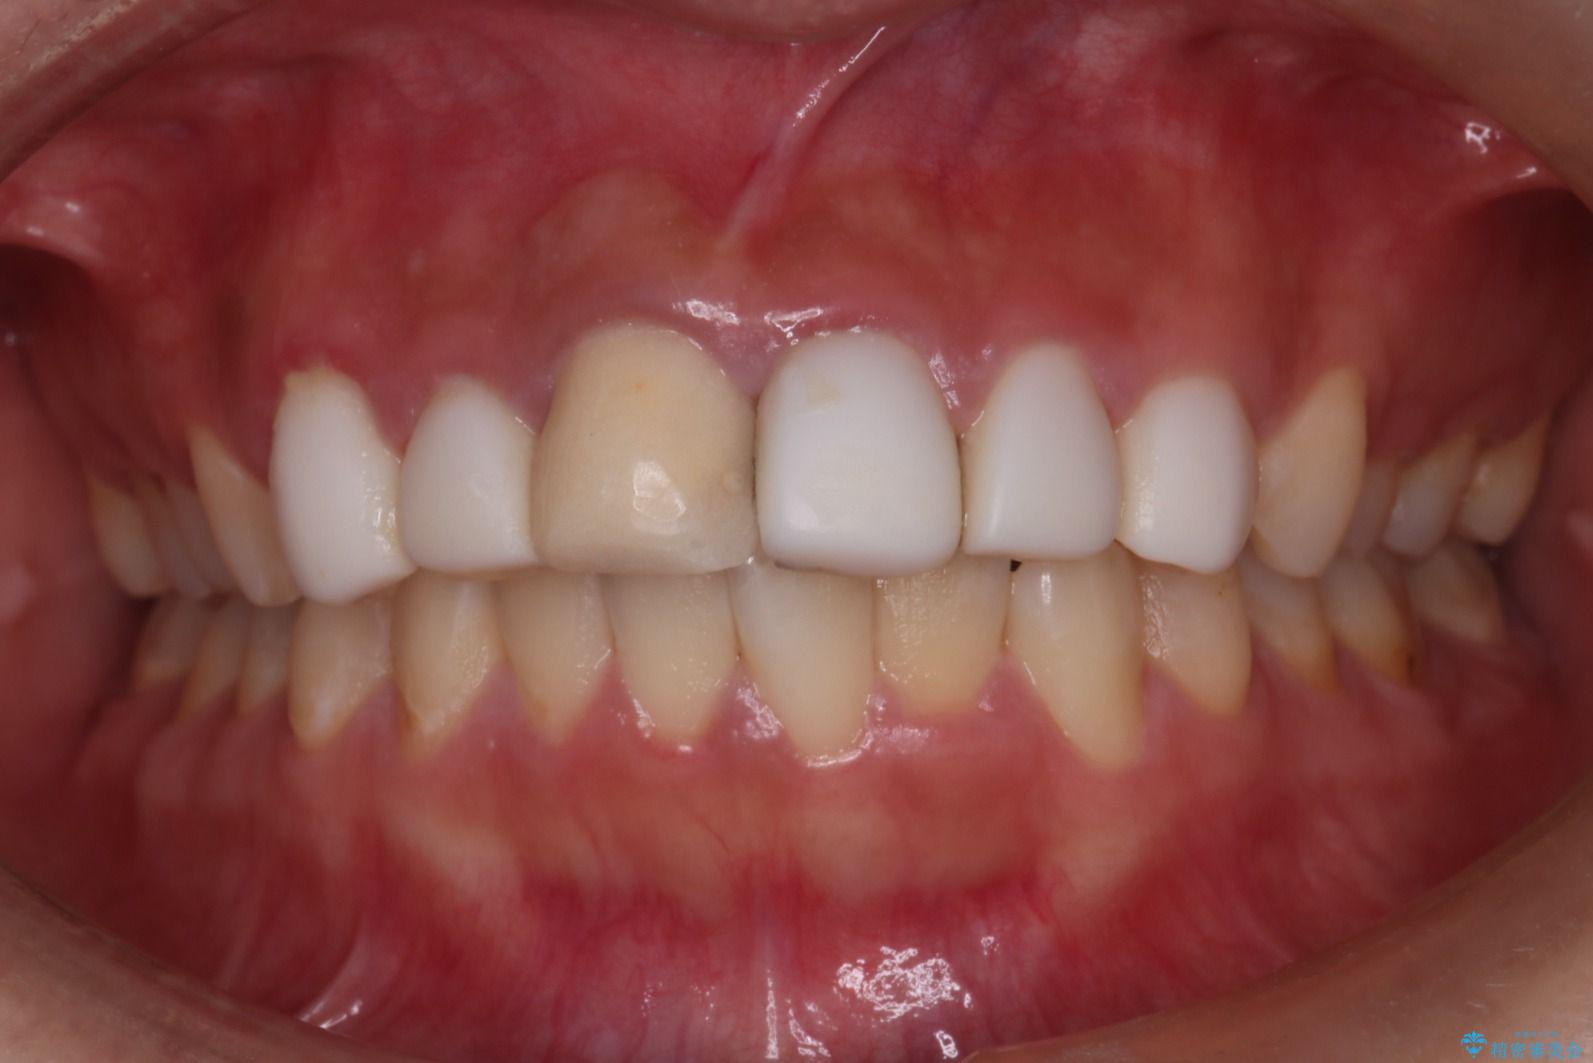

- 他院で治療した前歯の色が気になるということで来院された患者様です。前歯に色の差があり、レントゲンから内部にう蝕も見られたため、審美性に優れ、う蝕になりにくいオールセラミッククラウンで治療いたしました。

清掃性も上がったおかげで、歯肉の状態も良好に保てています。

色の調和もとれたので非常に満足いただけました。